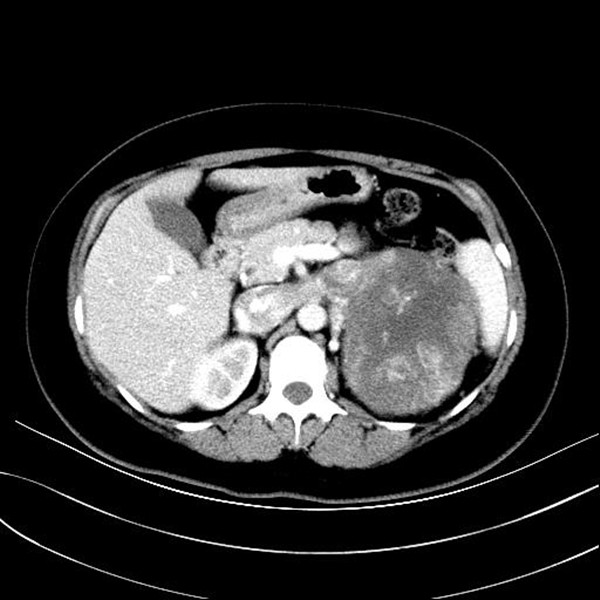

患者赫某,女性,25岁,以“体检发现左肾上腺占位1周余”之主诉入院。入院后检查提示肾上腺肿瘤相关检查:VMA、肾素、血管紧张素均明显增高。肾上腺MRI及CT提示:左肾上腺区异常强化肿块,大小约13.6×10.5cm,左肾静脉及下腔静脉癌拴,瘤栓上缘达右心房入口处。诊断:左肾上腺恶性肿瘤、腔静脉癌栓(Mayo IV级)。